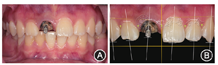

患者面部对称,中位笑线。口内检查可见11根管口金属螺纹桩,剩余牙体组织断裂至龈下1 mm;双侧前牙龈缘顶点连线不对称(图1)。口腔卫生良好,无探诊出血。前牙深覆

像;B:术前数字化美学分析

像;B:术前数字化美学分析锥形束CT示11根尖区有圆形低密度影,直径约6 mm,11颊侧骨板完整,厚约1 mm(图2)。